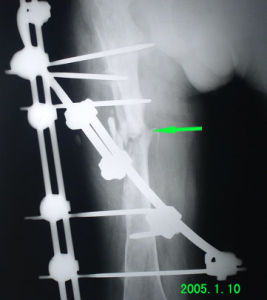

每一部位功能復位標準不盡一致,一般認為:骨折部的鏇轉移位,分離移位必須完全矯正。下肢骨折縮短移位在成人不超過1厘米,兒童不超過2厘米;長管骨橫形骨折 在骨幹部端對位達到1/3,乾酪端對位達到3/4以上,在幼兒向前或向後成角移位 因與關節活動方向相致,可在骨痂塑形期自行矯正,但在下肢,成人向前或向後成角移位不超過10度,兒童不超過15度,日後在骨痂塑形期也可自行矯正,向側方成角與關節活動方向垂直,日後不能自行矯正,必須完全復位。否則關節內外兩側在負重時所受壓力不均,日後可繼發創傷性關節炎,引起疼痛及關節畸形。上肢骨折部位不同要求不同,肱骨幹的輕度畸形,對功能影響不多,前臂雙骨折就要求對位對線都好,否則將影響前臂鏇轉功能。